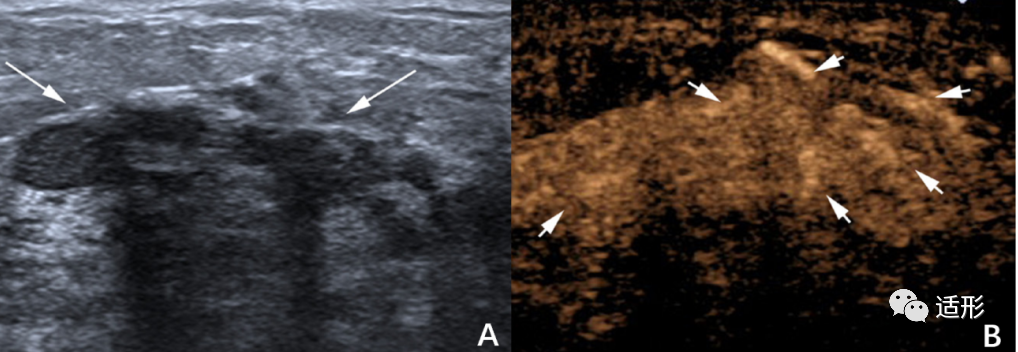

常规超声结合超声造影的准确性较高。超声造影上恶性NML表现为早期增强、高增强、强化不均匀、周边呈蟹足样,增强后的范围较二维测量范围增大(图5)。另外,超声造影病变内部出现放射状血管或穿支血管,也对诊断恶性NML有一定帮助(图6)。这些恶性NML的超声造影的表现与肿块型乳腺癌的相似,与恶性病变通常伴随新生血管形成,微血管密度增加有关。但需注意的是,部分慢性乳腺炎可表现为NML,其在超声造影表现为高增强,可能会导致假阳性的出现[8] 。部分文献报道粘液癌也可表现为NML,超声造影上呈等增强、不均匀强化或仅周围强化,强化后范围无明显增大,可能造成假阴性的出现。与肿块型病变不同的是,良性NML中有超过50%的病变超声增强呈现为不均匀强化,而在良性肿块型病变中多表现为均匀性强化。另外,无论良性或恶性NML,病灶最常表现为弥漫性强化。而在肿块型病变中,病变常表现为向心性或离心性强化。

图6. 49岁女性,超声提示非肿块型病变,呈低回声(右图长箭头),超声造影显示病变高增强、增强后范围增大,可见放射状穿支血管(左图短箭头)。病理诊断:浸润性导管癌[10]